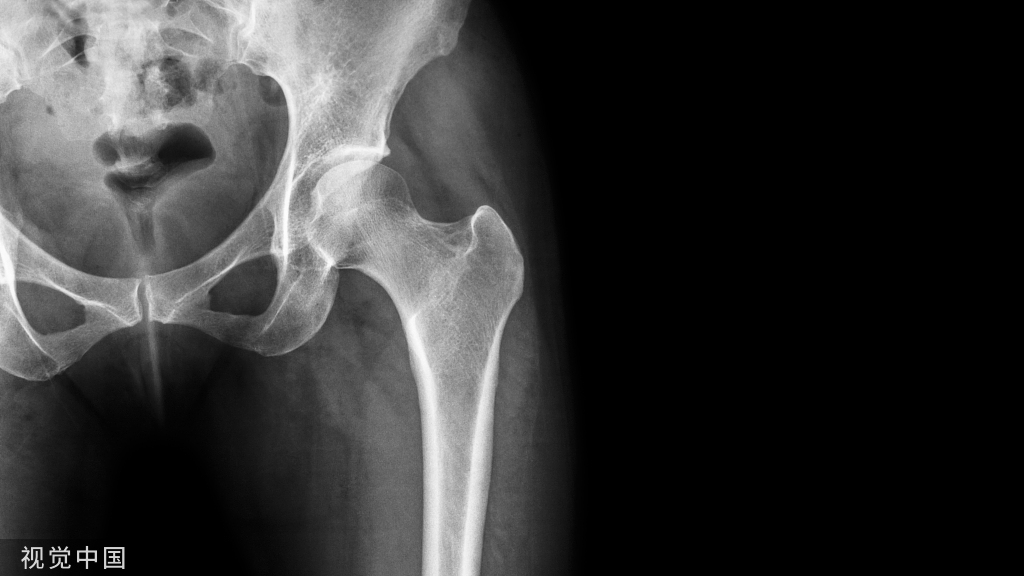

病史58岁男性,车祸后左侧骨盆疼痛。(A 58-year-old man with left sided pelvic pain following car accident.)

影像学表现股骨和骨盆骨可见多发小圆形硬化灶,X线片(a)和 CT图像(b)上都可见到左侧髂骨翼骨折。There are numerous small round sclerotic foci in the femurs and pelvic bones. Fracture of the left upper iliac wing is seen on both the radiograph (a) and CT image (b).

讨论骨斑点症的硬化灶通常小于广泛成骨性转移瘤或结节性硬化症的病灶。The sclerotic foci in osteopoikilosis are typically smaller that those seen with diffuse osteoblastic metastases or tuberous sclerosis.

• 是一种以关节周围骨性区域的多发小硬化灶(骨岛)为特点的硬化性骨发育不良。Sclerosing bone dysplasia characterized by numerous small sclerotic foci (bone islands) in periarticular osseous regions.

• 骨盆是最常见的受累部位。Pelvic bones are the most common site of involvement.